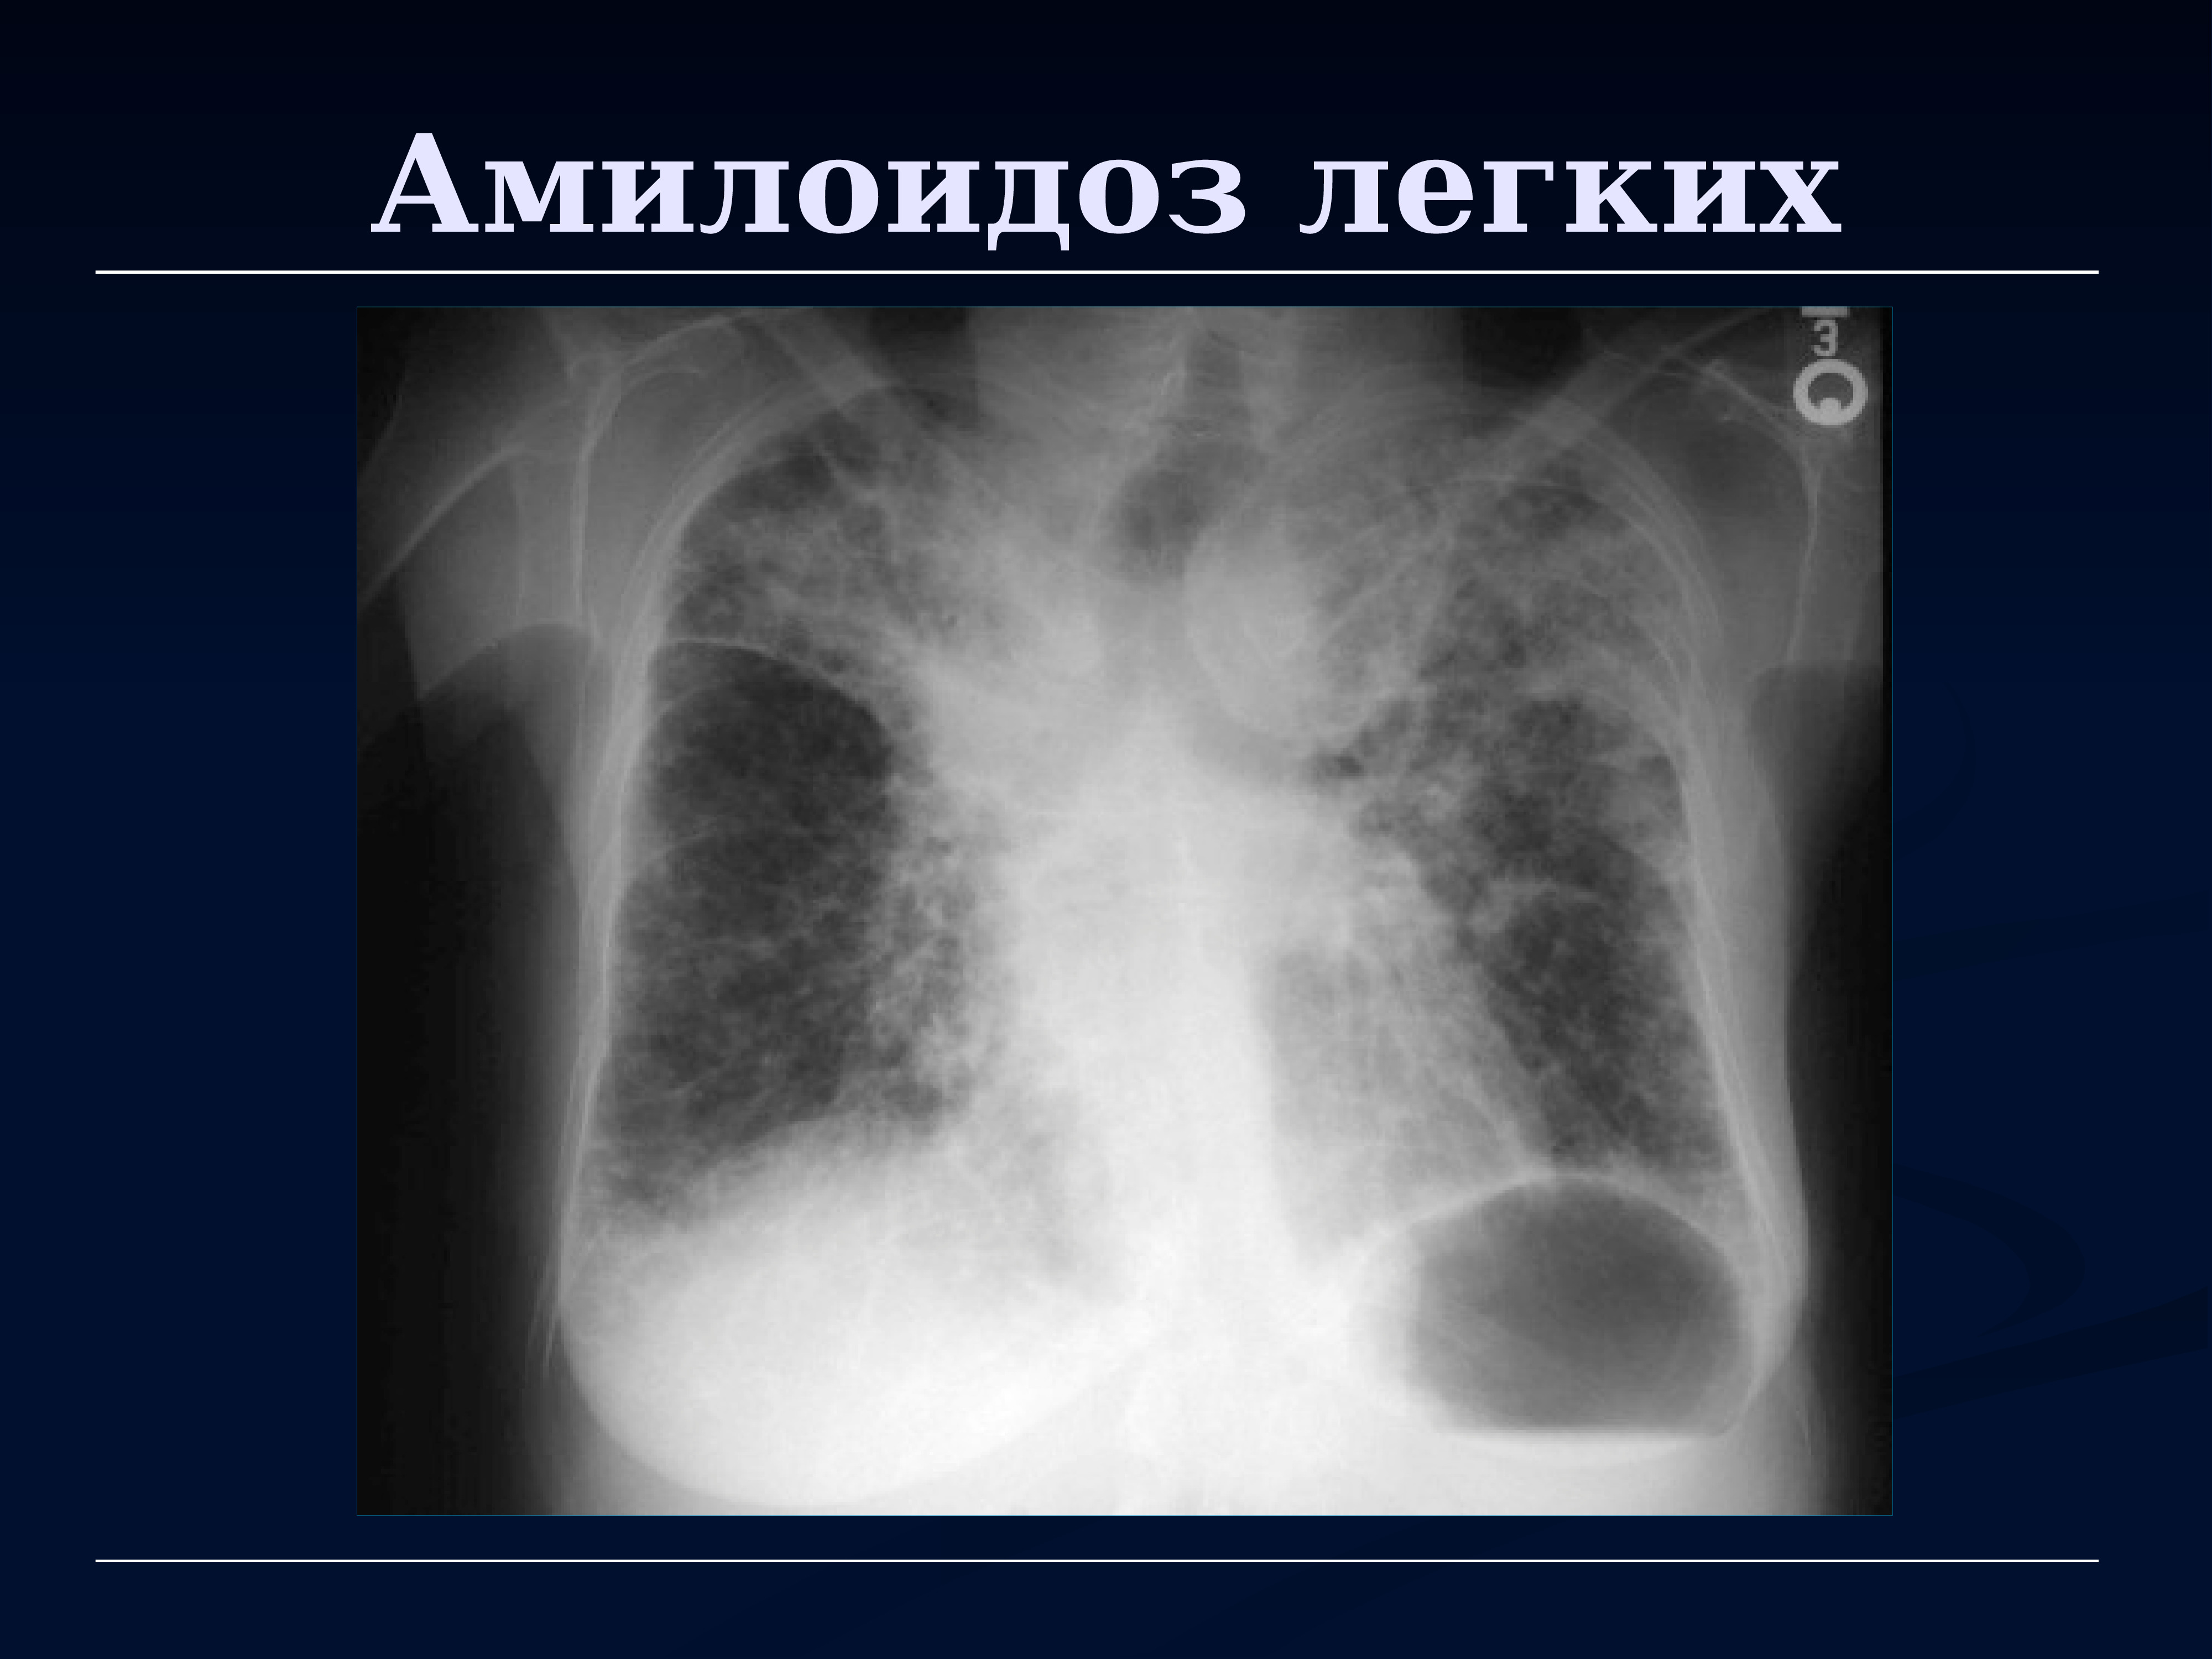

Attr амилоидоз

Attr амилоидоз 117 фотографий